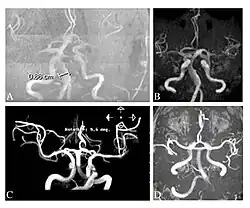

-

Die axiale MRT des Gehirns eines 27-jährigen Morbus-Fabry-Patienten mit ischämischem Schlaganfall zeigt den Schlaganfall in der linken zerebellären Hemisphäre. Der Patient wies sonst keine Symptome der Erkrankung auf. -

Hyperintensitäten der weißen Hirnsubstanz, lakunare Hirninfarkte und Mikroblutungen.

A) Die axiale MRT zeigt vielfältige Läsionen der weißen Hirnsubstanz in der zerebralen Hemisphäre eines 53-jährigen männlichen Patienten mit einem Fazekas-Score von 3.

B) Lakune und Mikroblutungen bei demselben Patienten. -

Die T1-gewichteten sagittalen (A) und axialen (B) MRTs zeigen ein symmetrisch hohes Signal im Thalamus (das sogenannte Pulvinar Sign) eines 66-jährigen männlichen Patienten. (C) und (D), ebenfalls T1-gewichtet, zeigen das Pulvinar Sign bei einem 42-jährigen Patienten. -

Die Time-of-Flight-Magnetresonanzangiographien von vier Morbus-Fabry-Patienten zeigen erweiterte (ekstatische) Blutgefäße (Dolichoektasien der vertebrobasilären Zirkulation).